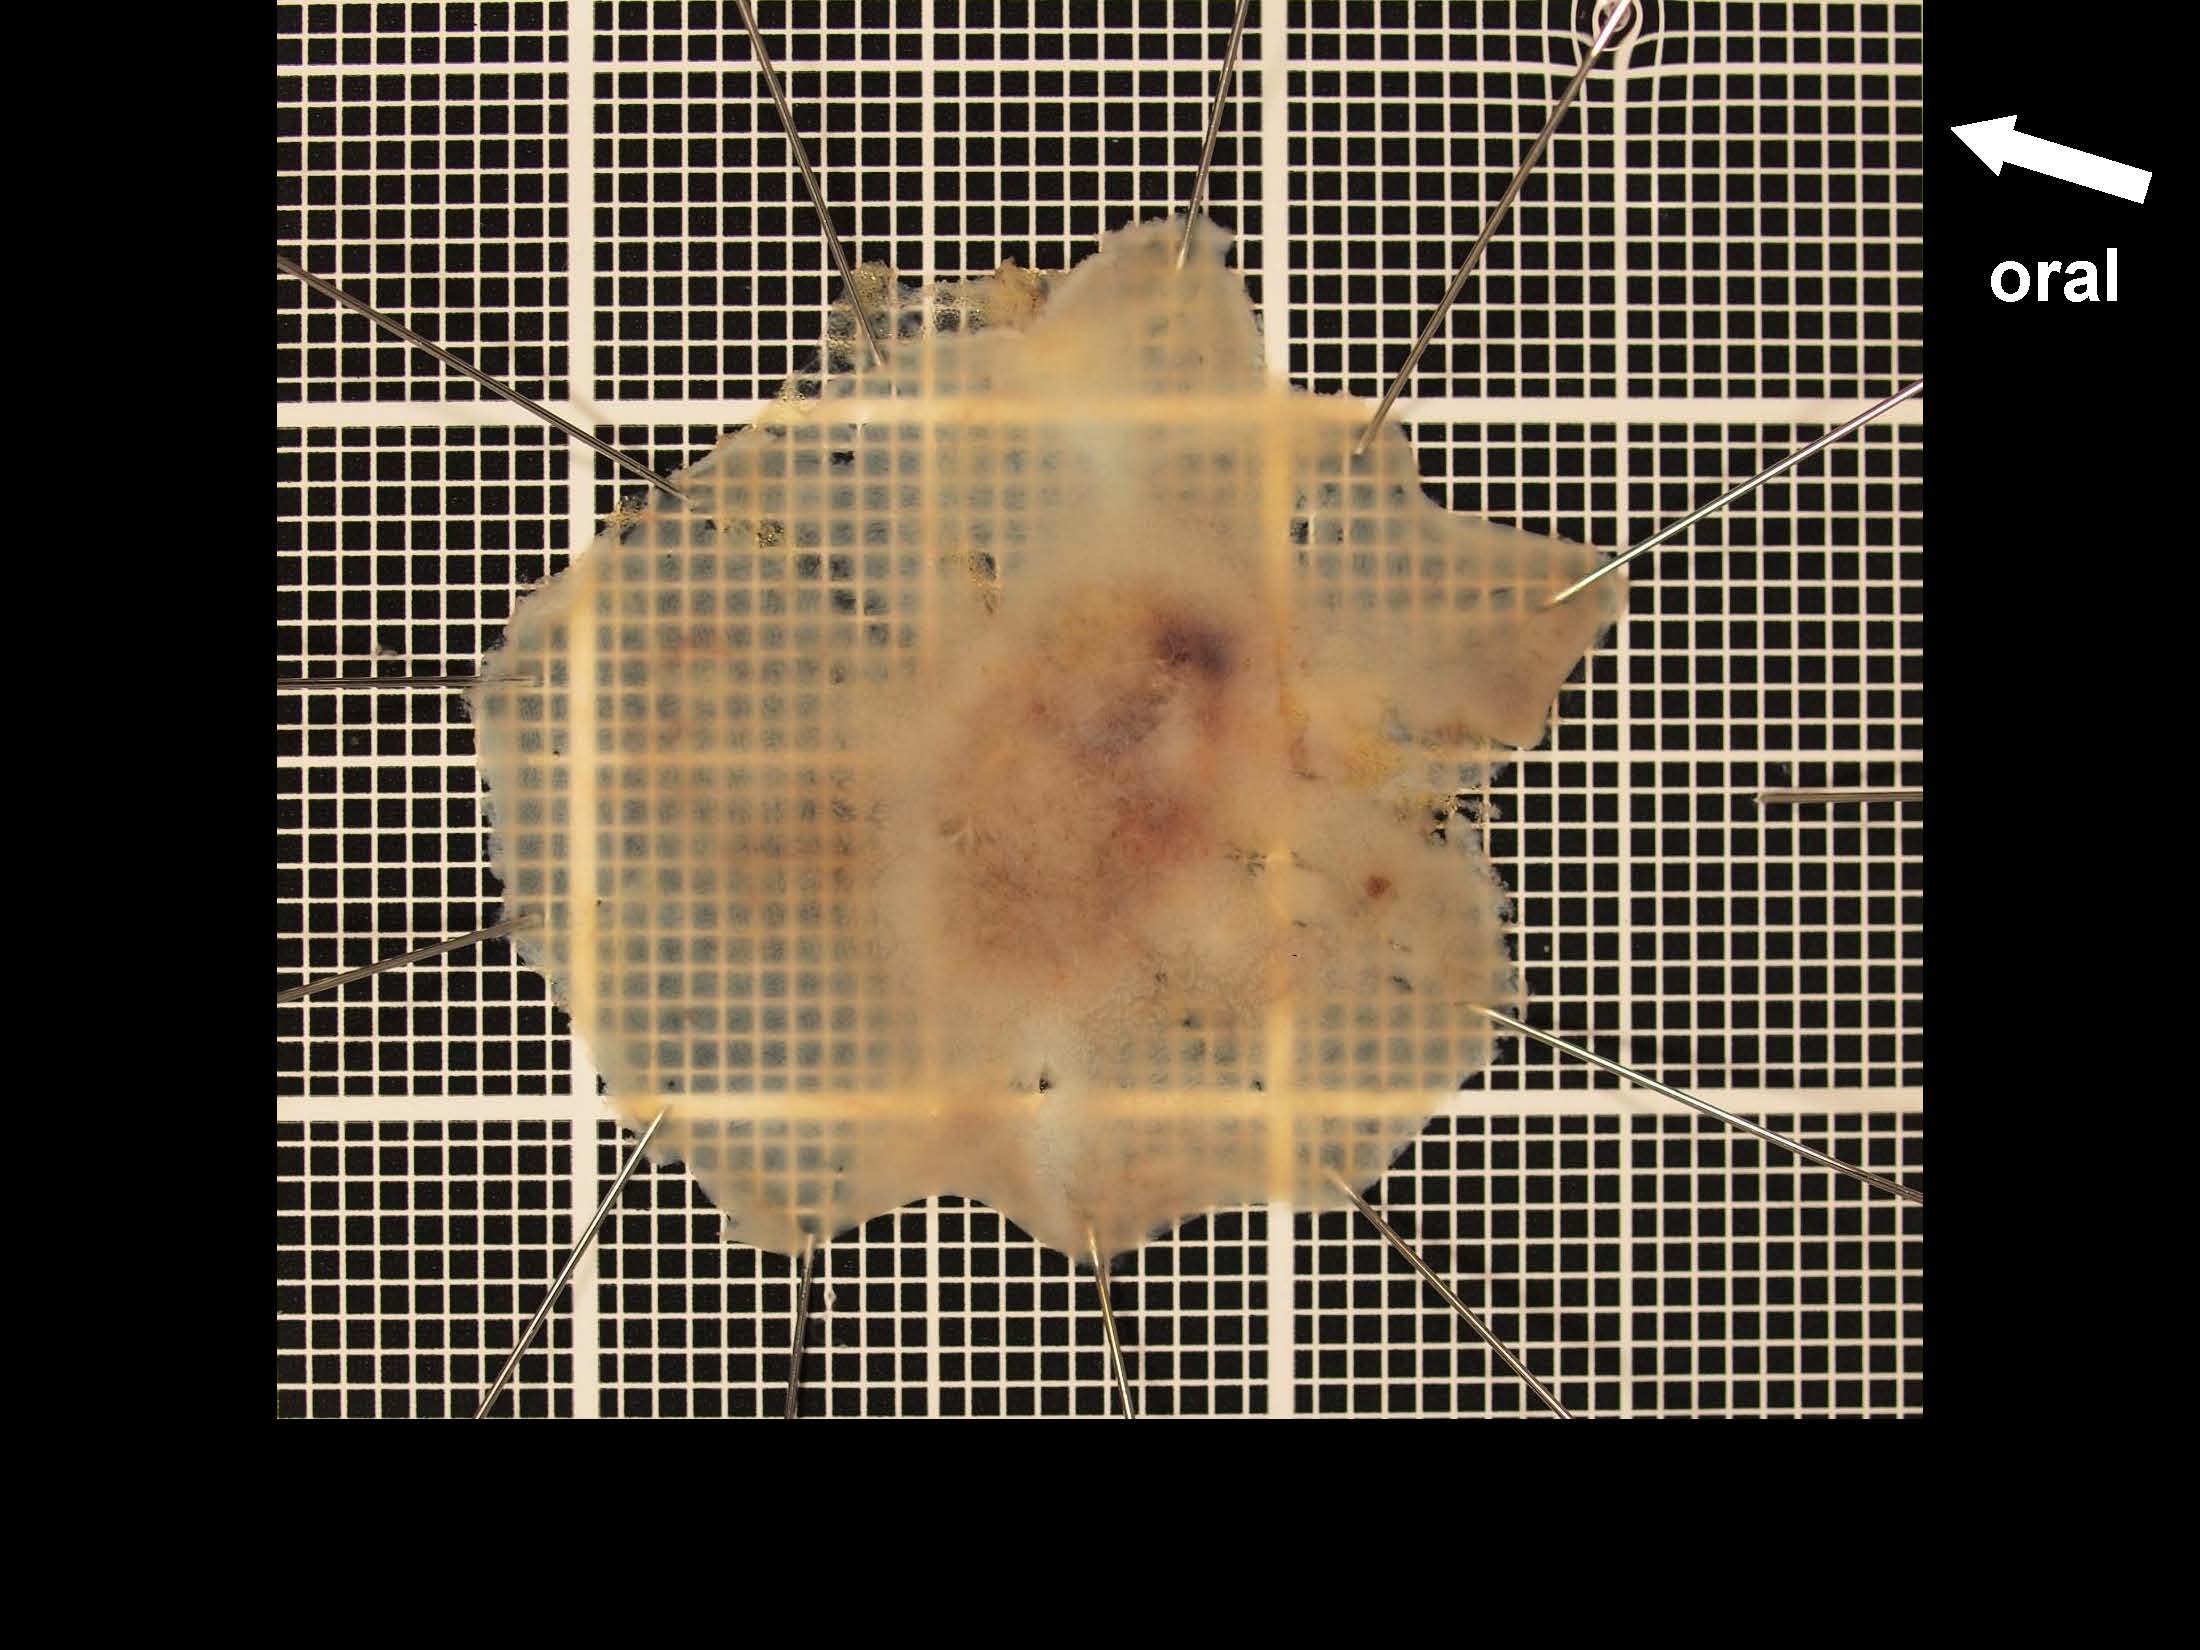

内視鏡検査・治療

消化管Mapping

消化管Mapping~大腸~

消化管Mapping~大腸~ 2021.10.27